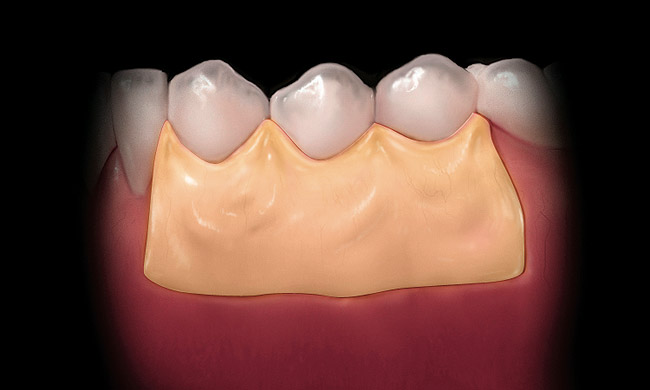

If acelluar connective tissue is used, place the rehydrated piece of acellular dermal allograft on the site to allow blood to contact the material, making sure to touch both sides to the recipient bed. The side that retains the coloration from the blood (red side) should be placed over the recipient bed facing away from the roots. This technique places the “white” side (basement membrane side) toward the root surface to be grafted. The connective tissue is placed over the root exposure and secured with 5-0 polyglycolic acid (PGA) sutures (Figure 8).12 The apical boarder of the graft is not sutured so that apical tension is not placed upon the graft during function as healing occurs.13

The flap should be coronally positioned over the graft and secured with 4-0 PGA (3/8 circle reverse cutting needle) (Figure 9). Using a sling suturing technique, the coronal flap margin is fixated to the lingual soft tissue.14,15 Releasing incisions and Burrow’s triangles are secured with 5-0 PGA (1/2 circle reverse cutting needle). Interrupted sutures are then used to secure the lateral graft borders. It is not critical that all of the graft is covered, and having some portion of the graft exposed at the gingival margin will not affect healing.

Figure 8  The connective tissue is sutured over the recipient bed.

Figure 8

Figure 9  The flap is repositioned and sutured in place.

Figure 9